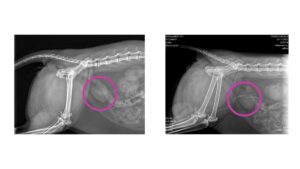

まずレントゲンを撮りました。

すると、

膀胱に石が3つある

と言われました。

エコーをしたら

石がなかった

のだそうです。

綺麗さっぱり無くなってる🤭

手術の先生も

「こんなことはありえない」

と言っていました。